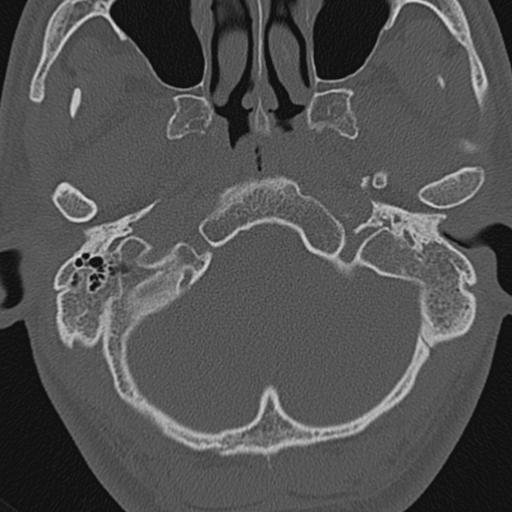

以下是引用zxl51642在2009-8-25 13:37:00的发言:[br]1、左侧慢性硬化型中耳乳突炎(中耳鼓室腔及听小骨受累),并胆脂瘤形成;2、左侧外耳道软组织密度影填塞,考虑炎性肉芽肿,建议结合临床;3、右侧颈静脉窝较左侧明显扩大,不排除颈静脉球瘤,建议mr进一步检查。

以下是引用随光逐影在2009-8-25 19:05:00的发言:[br]1)左侧慢性中耳乳突炎(肉芽肿或胆脂瘤形成),左侧外耳道炎性肉芽肿。2)右侧颈静脉球高位。